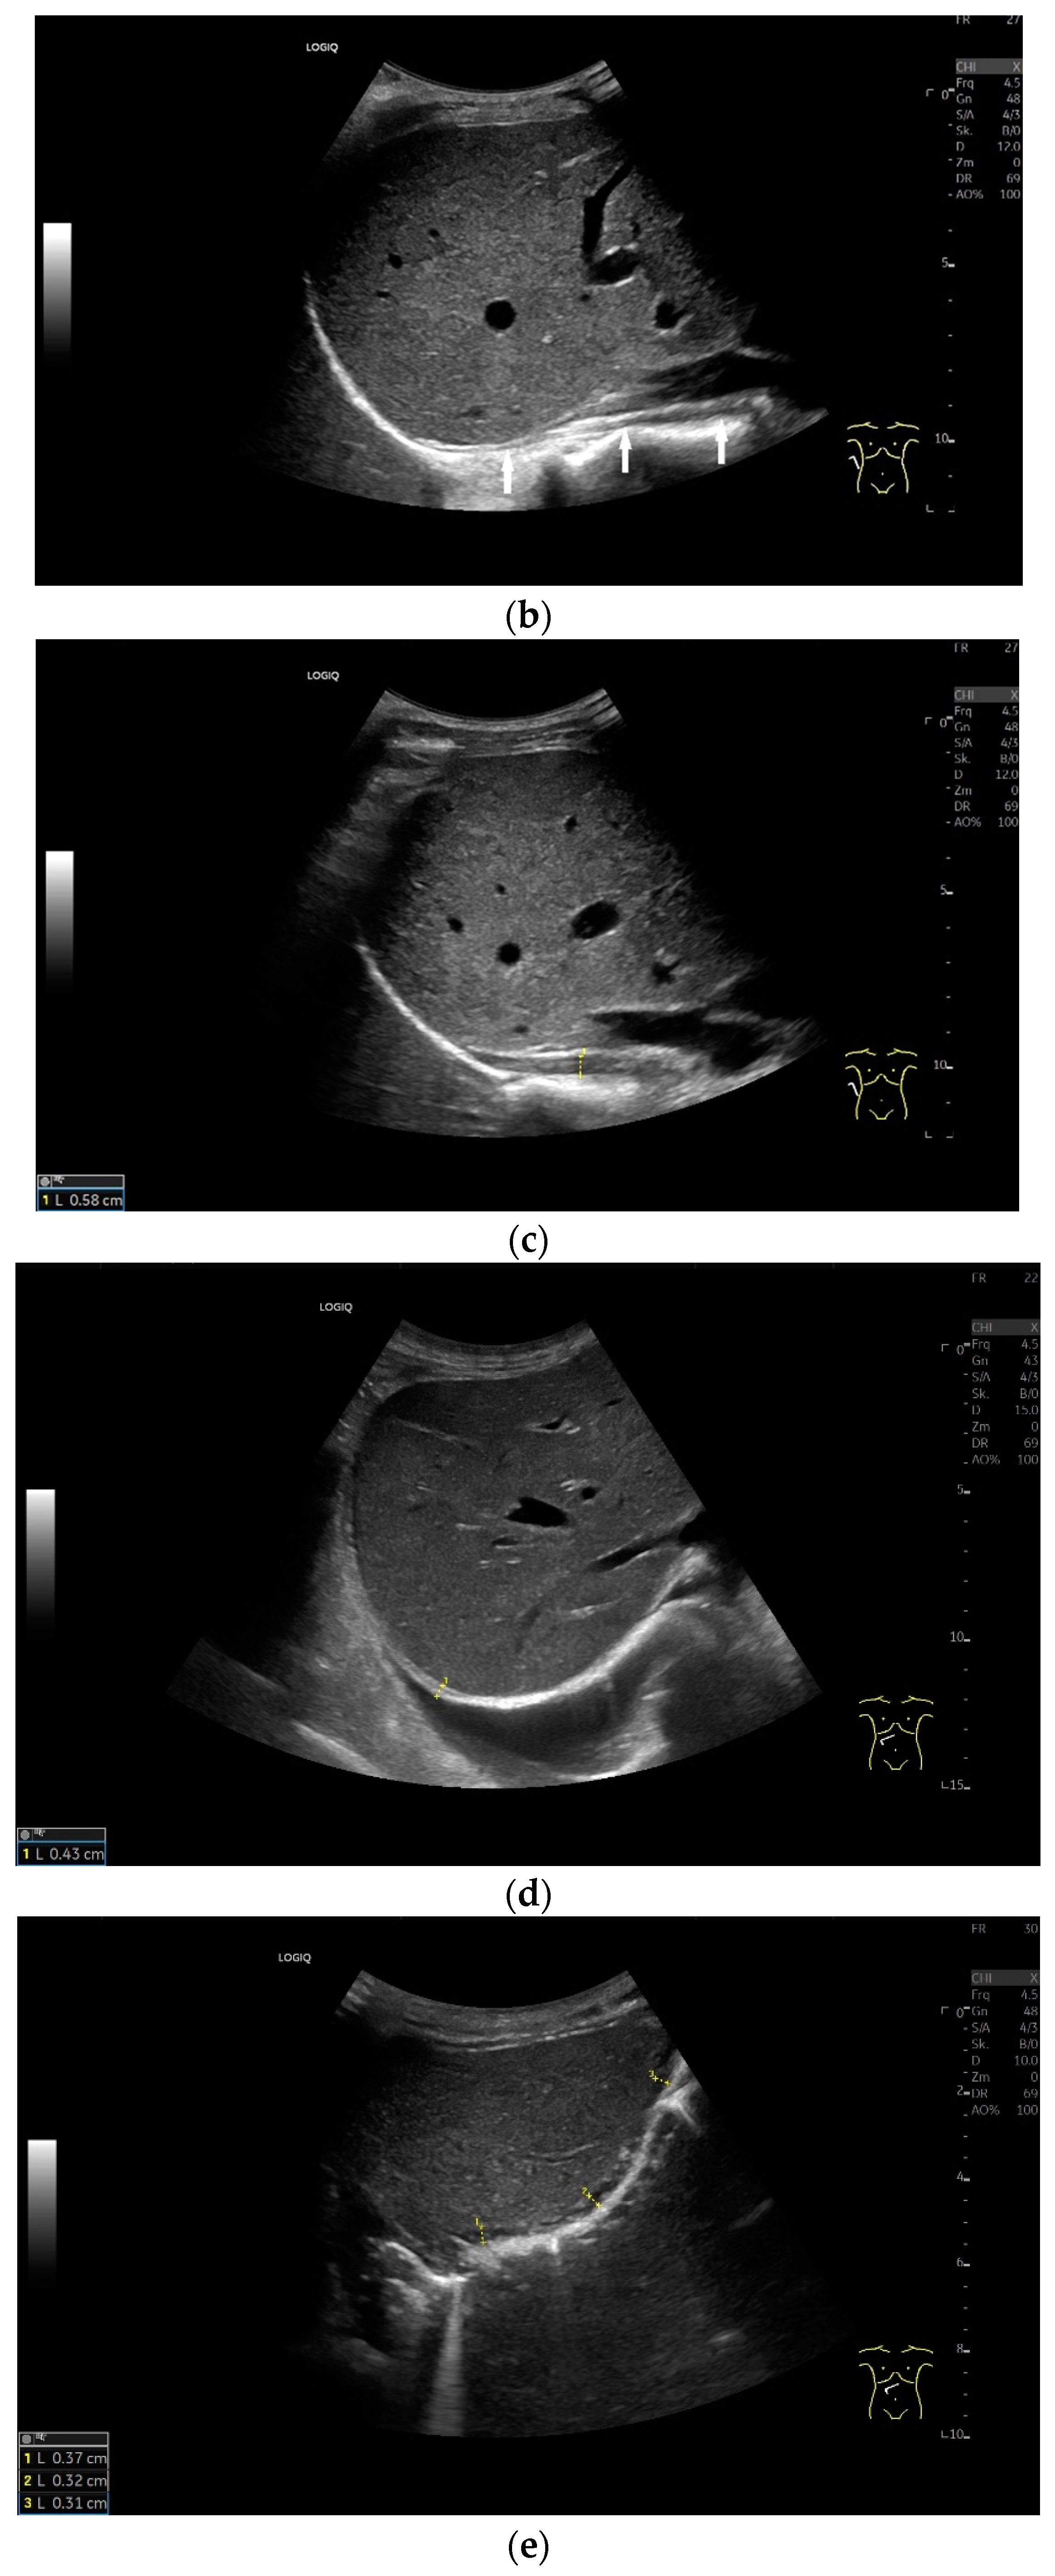

Lateral transducer position in the zone of apposition: The transducer is positioned longitudinally and laterally in the area of the mid-axillary line or slightly ventral to it between the anterior and mid-axillary lines, approximately in the 8th or 10th intercostal space. The diaphragmatic reflex is located on the inner side of the ribs below the pulmonary glide with pulmonary reverberations. This localization of origin of the diaphragm from the inner side of the rib cartilage is referred to as the zone of apposition (Figure 3). As this localization is only a few centimeters below the skin surface, high-resolution linear transducer use is highly recommended. In this position, the diameter of the diaphragm is measured during inspiration and expiration [2,3,4,5] (Figure 4). The thickness of the diaphragm varies, with caudal parts being thicker than cranial parts. The measurement of diaphragm thickness is highly variable depending on the intercostal space chosen, with thickness varying by up to 6 mm between the intercostal spaces [6]. It is therefore important to select the same position for comparable measurements and, if necessary, to mark the location for the transducer position [7]. Obesity limits assessment of the diaphragm [2].